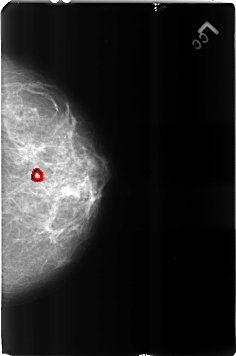

B_3160_1.LEFT_CC

FILE: B_3160_1.LEFT_CC.OVERLAY

TOTAL_ABNORMALITIES 1

ABNORMALITY 1

LESION_TYPE CALCIFICATION TYPE LUCENT_CENTERED DISTRIBUTION N/A

ASSESSMENT 2

SUBTLETY 4

PATHOLOGY BENIGN

TOTAL_OUTLINES 1

BOUNDARY

LEFT_CC LINES 4624 PIXELS_PER_LINE 3056 BITS_PER_PIXEL 12 RESOLUTION 50 OVERLAY